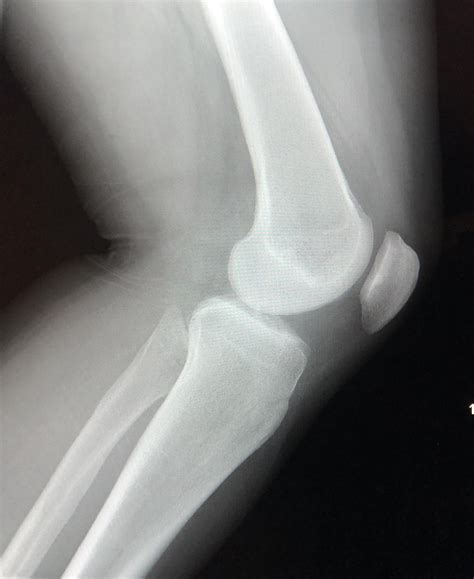

Lateral Knee Xray

A Lateral Knee Xray is a type of radiographic imaging that captures a side view of the knee joint. This view is essential for evaluating the alignment of the bones, the condition of the joint spaces, and the presence of any abnormalities such as fractures, dislocations, or arthritis. The lateral view complements other views, such as the anteroposterior (AP) and oblique views, to provide a comprehensive assessment of the knee.

Interpreting a Lateral Knee Xray requires a trained eye and knowledge of knee anatomy. Here are some key points to look for:

• Bone Alignment: Ensure that the bones are properly aligned. Any deviation can indicate a fracture or dislocation.

• Joint Spaces: Check the joint spaces for any narrowing, which can suggest arthritis or other degenerative conditions.

• Fractures: Look for any breaks or cracks in the bones, which can indicate a fracture.

• Soft Tissue Signs: While not always visible, soft tissue injuries can sometimes be inferred from the presence of joint effusion or other indirect signs.